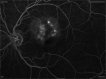

Figures